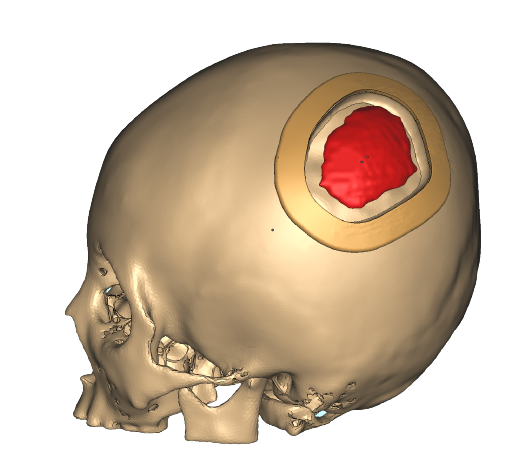

Medical

Medical